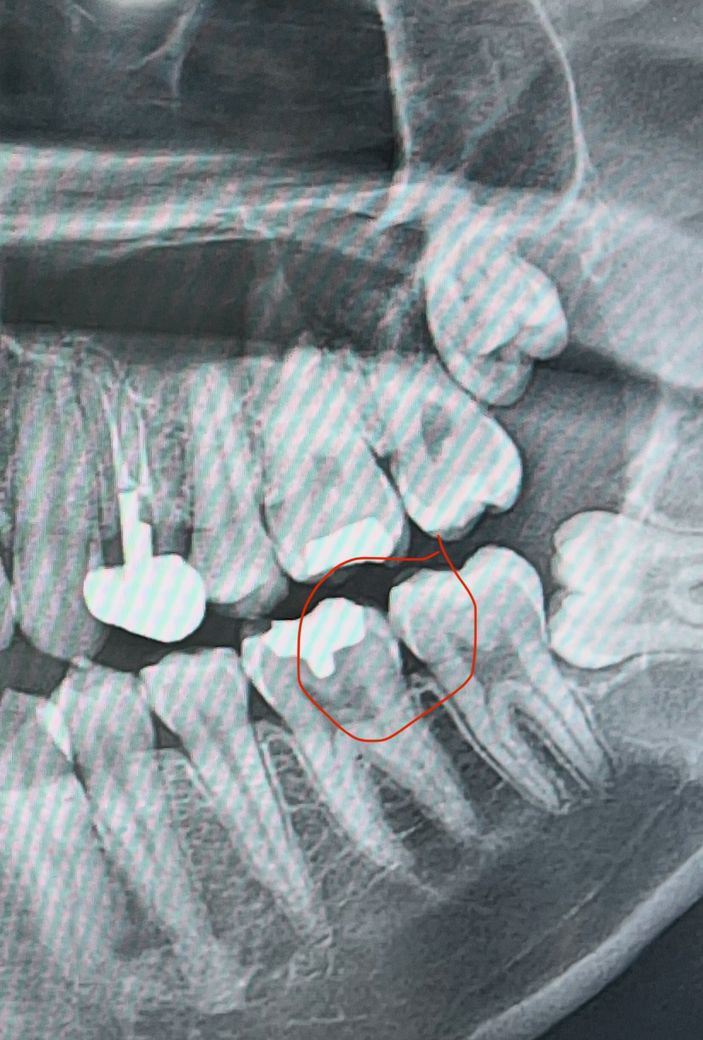

이 엑스레이 사진 인접면 충치가 맞을까요?

두 군데 다 가보고 엑스레이 찍었는데 직접 보고 기구로 긁으셨는데 검은색이 보이긴 하는데 충치가 아니고 착색이니까 양치 잘 하라고 하시네요.. 엑스레이상으로도 문제 없다고 하시는데 이 부분이 충치일까요? 착색이 저런식으로 보이기도 하나요? 그리고 만약 충치가 맞다면 6개월 이후에 검진할때 훨씬 심해져있지는 않을까요? 인접면 충치가 진행이 빠르다고 해서요..

경미한 충치일 수도 있으며, 말씀하신 것처럼 착색일 수 있습니다. 또한 경미한 충치라도 관리가 잘 된다면 더 이상 진행이 되지 않을 수 있습니다. 해당 사진에서는 인접면 충치를 정확히 판단하기 어려우며, 보통은 standard view 사진을 찍어서 정밀 검사를 하면 알 수 있습니다. 충치는 단기간에 진행되지 않으며 6개월 뒤에 다시 검사해봐도 괜찮습니다.

파노라마 사진으로는 판단하기는 어렵고 작은 엑스레이 사진을 찍어보셔야될것같습니다. 치아 사이 충치가 의심되긴합니다.

엑스레이 사진상 충치 가능성 있어보입니다 착색은 엑스레이상으로 나타나지 않고요 인접면 충치는 진행이 빠른것 맞습니다

사진으로 봤을 경우에는 인접면에 병서가 보이는 것처럼 보이기도 합니다. 하지만 해당 부위의 충치는 치아를 삭제해보지 않는 이상 정확히 확인하기 힘듭니다. 불편감이 없다면 치실을 이용해서 관리를 해보는 것을 권유드립니다.